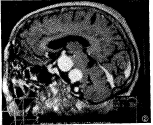

【摘要】 目的 评价三维梯度回波(3D-SPGR)增强MRA对颅脑巨大动脉瘤的应用价值。 材料与方法 16例共18个巨大动脉瘤,包括颈内动脉虹吸部10个,椎动脉4个,基底动脉1个,大脑前动脉1个,前交通动脉1个,后交通动脉1个。MR机为GE 1.5T超导型及相应工作站。增强3D-SPGR轴位扫描后,进行矢、冠、斜位等多平面重建(multiplanner reconstruction,MPR),并与传统3D-TOF法MRA进行对比。 结果 3D-SPGR增强MRA及MPR能较好地显示动脉瘤的真实大小及瘤内成分,显示动脉瘤颈及其与载瘤动脉的关系,还能明确动脉瘤与周围神经血管及脑实质等结构的关系。 结论 3D-SPGR增强MRA对颅脑巨大动脉瘤有较大的应用价值,更优于传统MRA。